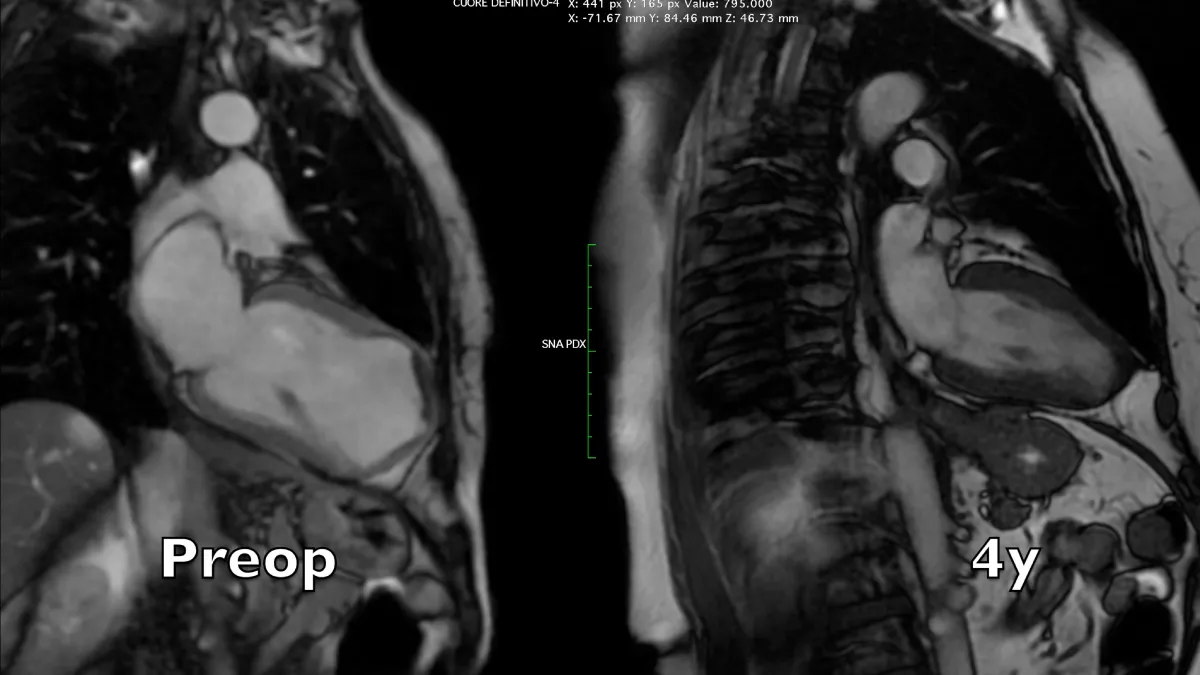

Figure 2: Magnetic resonance long axis systolic frames at two controls, preoperative and 4 years after the operation. A near-normal chamber geometry and wall thickening is evident. Note the reduction of left atrial volume, even in the absence of preoperative mitral regurgitation.

Video 2: Magnetic resonance four-chamber view, comparison between preoperative and 4 years controls.

Video 3: Magnetic resonance long axis view, comparison between preoperative and 4 years controls.

Video 4: Magnetic resonance short axis views, comparison between preoperative and 4 years controls. Note the evident apical and chamber reconstruction, and the remarkable improvement of global left ventricular systolic thickening and diastolic relaxation.

Figure 3: Magnetic resonance short axis systolic frames at two controls, preoperative and 4 years after the operation. The whole left ventricular chamber is restored and the remote myocardium regains its mechanics.

Preoperative imaging shows a very large dyskinetic region equal to around half of the ventricular chamber, conditioning a box-shaped ventricle with severely impaired global contraction, wall thickening, and diastolic function. Surgical reconstruction achieved an elliptic chamber with a normal volume and a new apex that were maintained along the years, gradually improving global ejection fraction and diastolic indices (Table 1), showing a positive remodeling induced by the optimised geometrical and functional parameters, left ventricular torsion included. Remote regions show a renewed, increased thickening granted by the better chamber geometry and fibers’ realignment, and the whole left ventricle shows a time-dependent restoration of its functional reserve, preoperatively hidden by the unfavourable functional conditions.